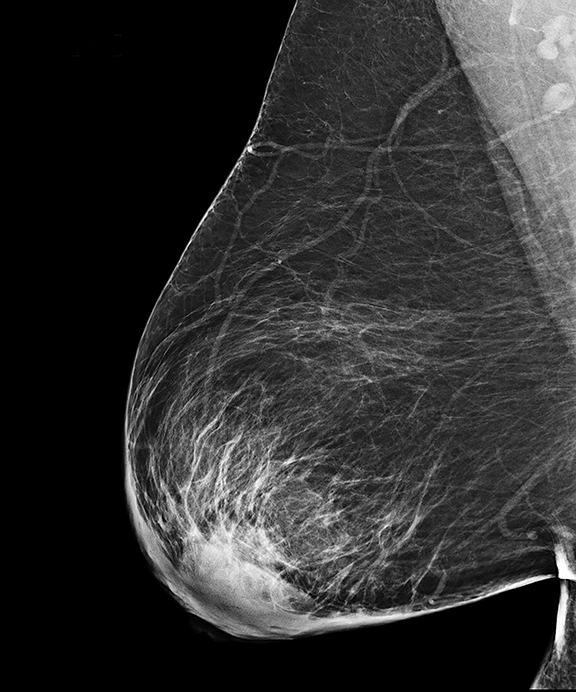

УЗИ молочных желез — информативный и безопасный метод диагностики, с помощью которого можно точно оценить состояние желез, обнаружить доброкачественные и злокачественные образования, уточнить диагноз. Это доступное по цене исследование безвредно и не несет лучевой нагрузки. Оно имеет большое значение в ранней диагностике заболеваний и нередко применяется в профилактических целях. На УЗИ может направить маммолог, онколог, эндокринолог, гинеколог.

Сделать УЗИ молочных желез можно в качестве первичной диагностики и для уточнения уже предполагаемого диагноза. Метод основывается на способности высокочастотных ультразвуковых волн с различной скоростью отражаться от тканей с разной плотностью.

С помощью ультразвуковой диагностики можно обнаружить следующие заболевания:

- воспалительные заболевания — мастит, абсцессы, лактостаз у кормящих женщин, мастопатии различного происхождения и типа — фиброзно-кистозные, диффузные и пр.;

- врожденные аномалии молочной железы;

- рак;

- кисты и доброкачественные опухоли;

Для оценки кровотока в тканях молочных желез используется доплерография. Данные, полученные в результате биопсии под контролем УЗ-аппарата, могут сказать о природе и характере образований в молочных железах.

Кому противопоказано

УЗИ практически не имеет противопоказаний. Однако важно отметить, что информативность обследования груди таким способом у женщин молодого возраста выше, поскольку ткани молочных желез с возрастом становятся более рыхлыми. Поэтому после 40 лет УЗИ в большинстве случаев сочетается с рентген-диагностикой (маммографией).